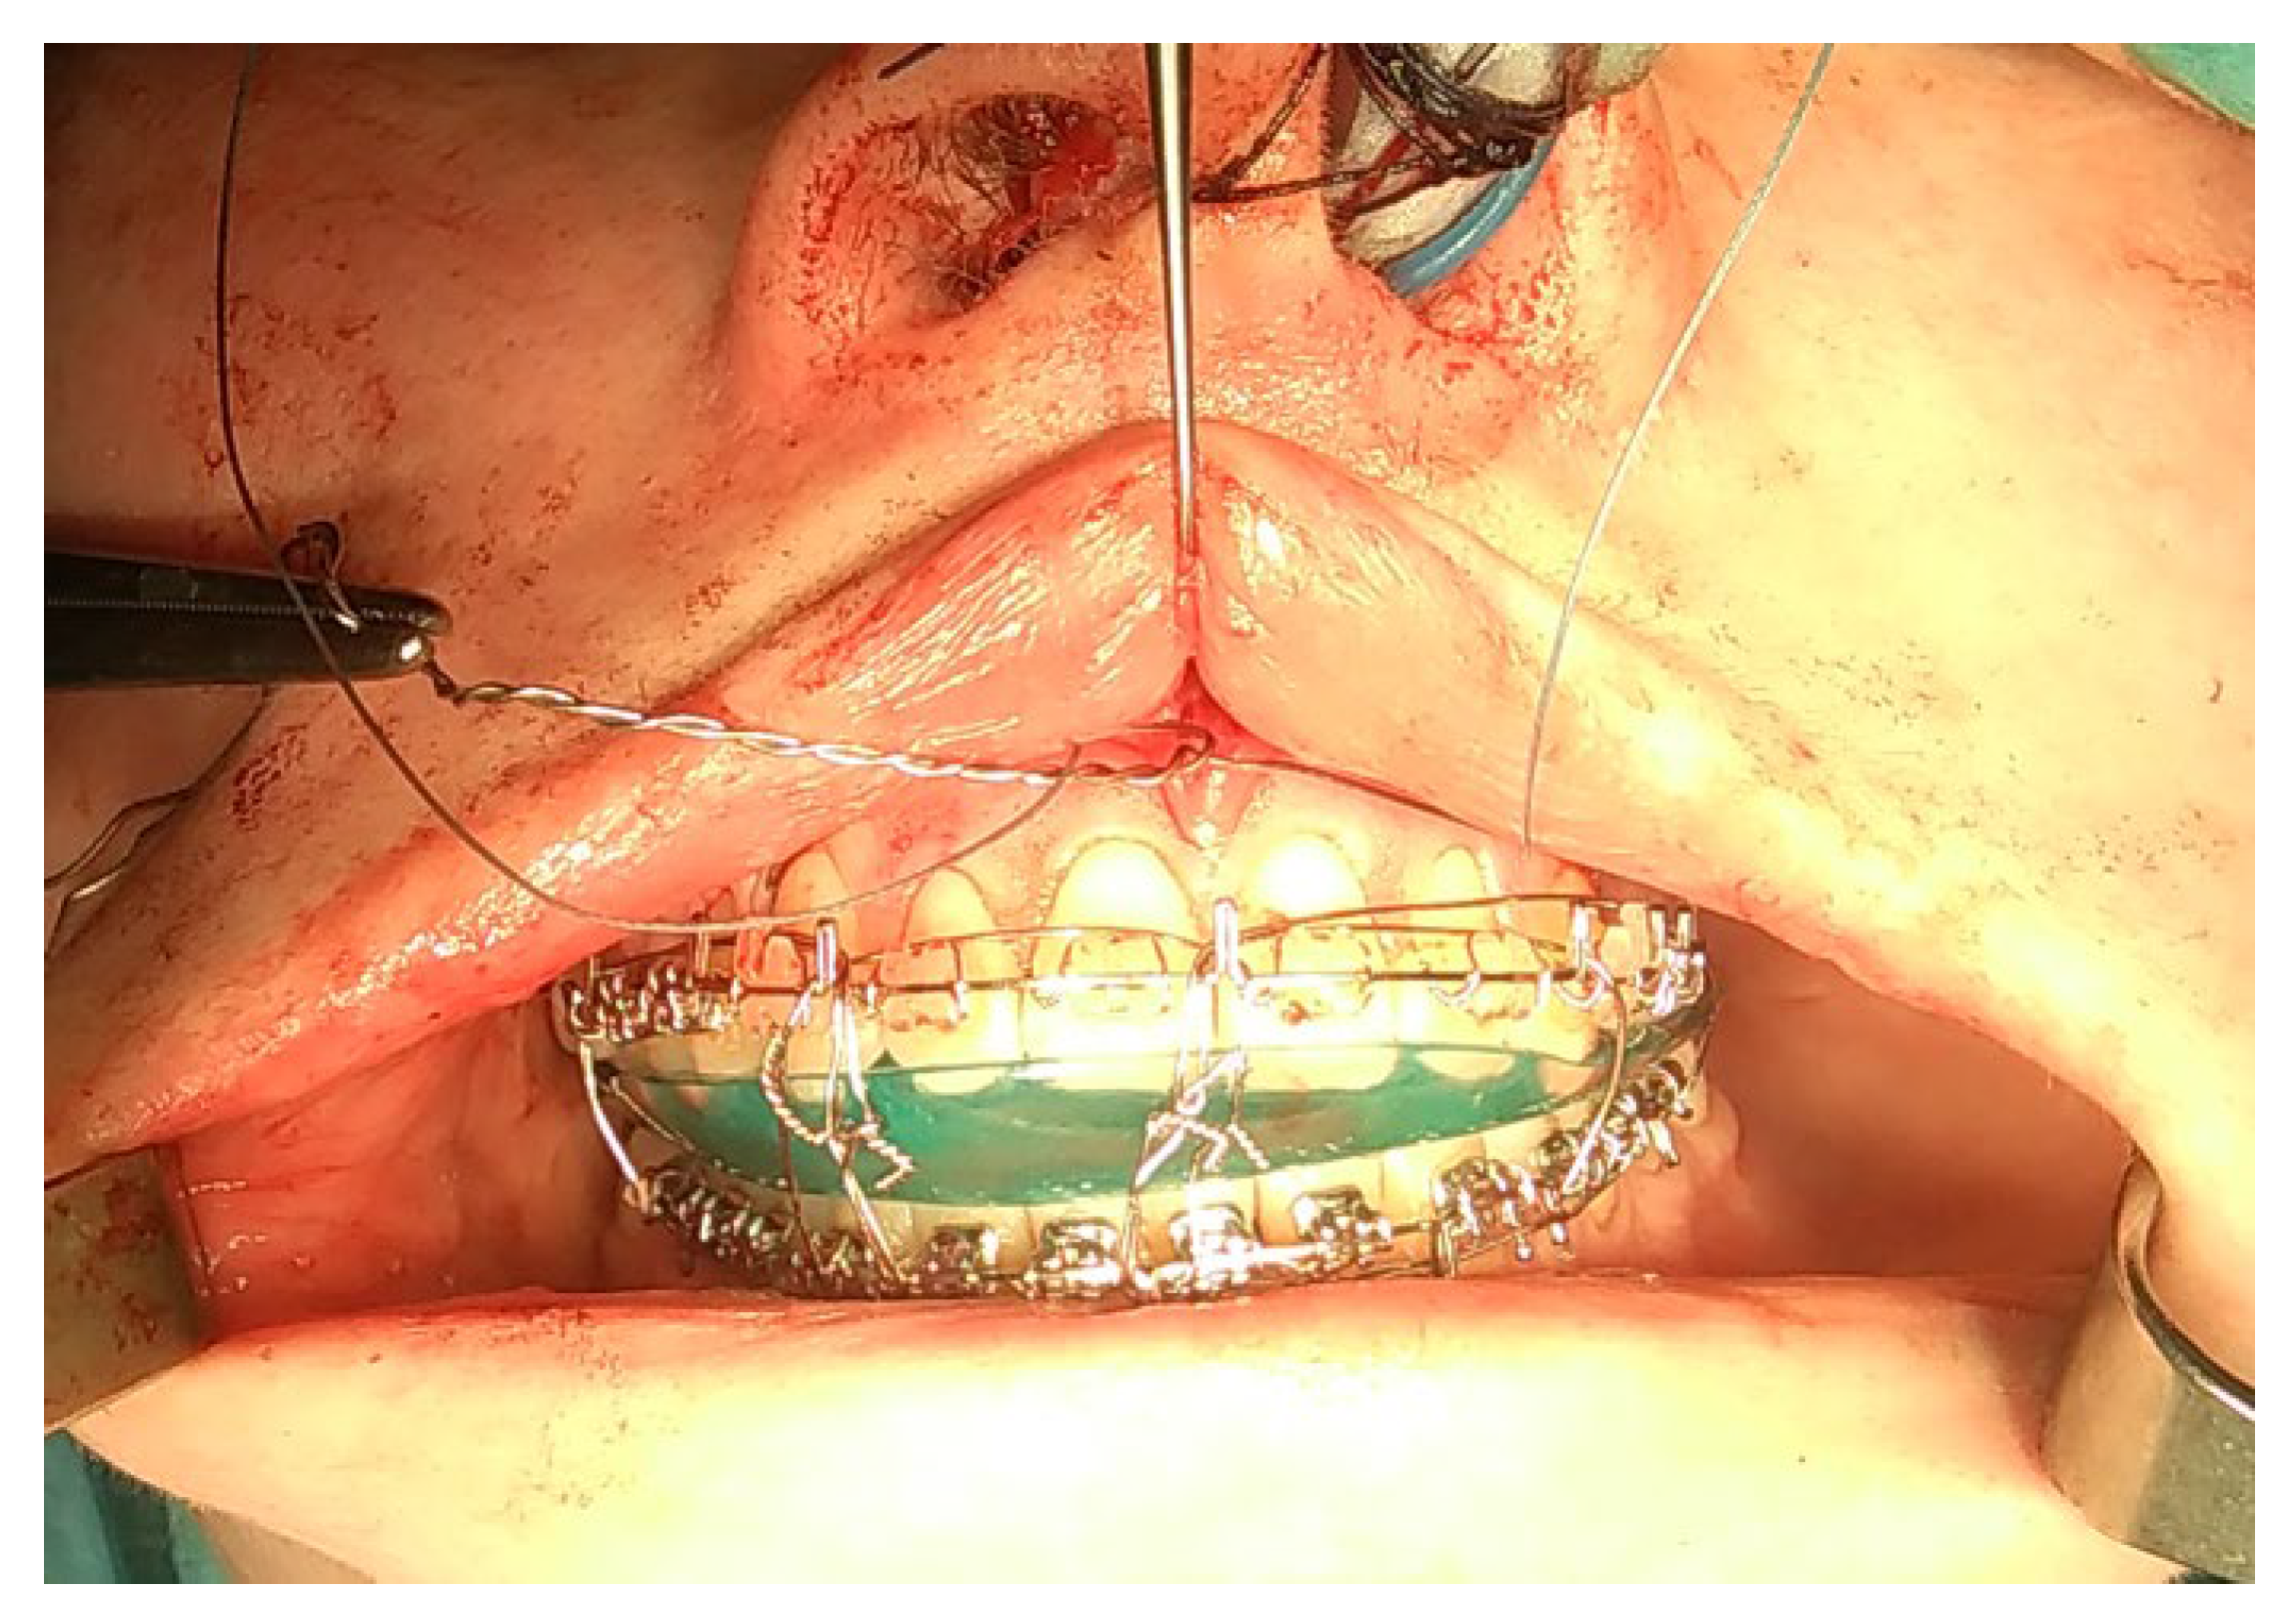

- A condylectomy with BSSO and Lefort I simultaneously was described by Wolford in 2002; however, some authors report operated TMJ joint instability, which might be related to the degree of excised bone and poor condyle stabilization with at least lateral pterygoid muscle reattachment or other, perhaps even related with IMF intramaxillary fixation devices to stabilize the occlusion [75] (Figure 9);

- (7)